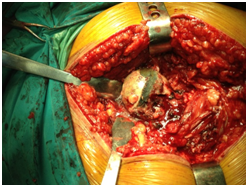

The patient was scheduled for surgery of total right knee arthroplasty. During the surgical approach of the knee we observed the dark pigmentation of the synovium, the bone cartilage, the quadriceps tendon and the menisci. This rare condition, characterized by many as ‘’Black Bone Disease’’, is accompanied by extensive destruction of the femoral condyles and the tibial Plateau due to arthritis. We performed a cemented total arthroplasty and sent pieces of the bones and the meniscus for histological examination (Figure 4).